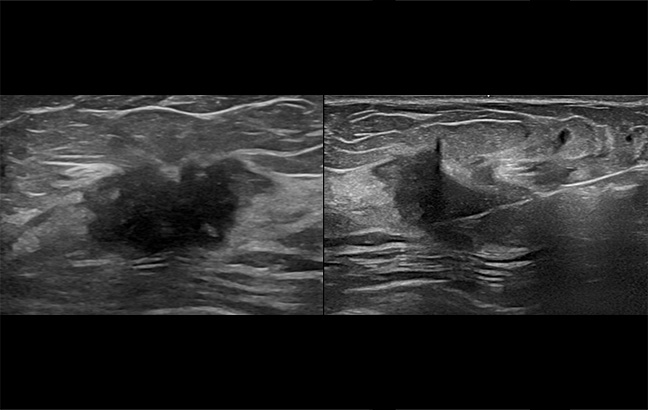

영상 검사에서 이상이 발견될 경우,

양성 종양인지 유방암인지 확진하기 위한 검사입니다.